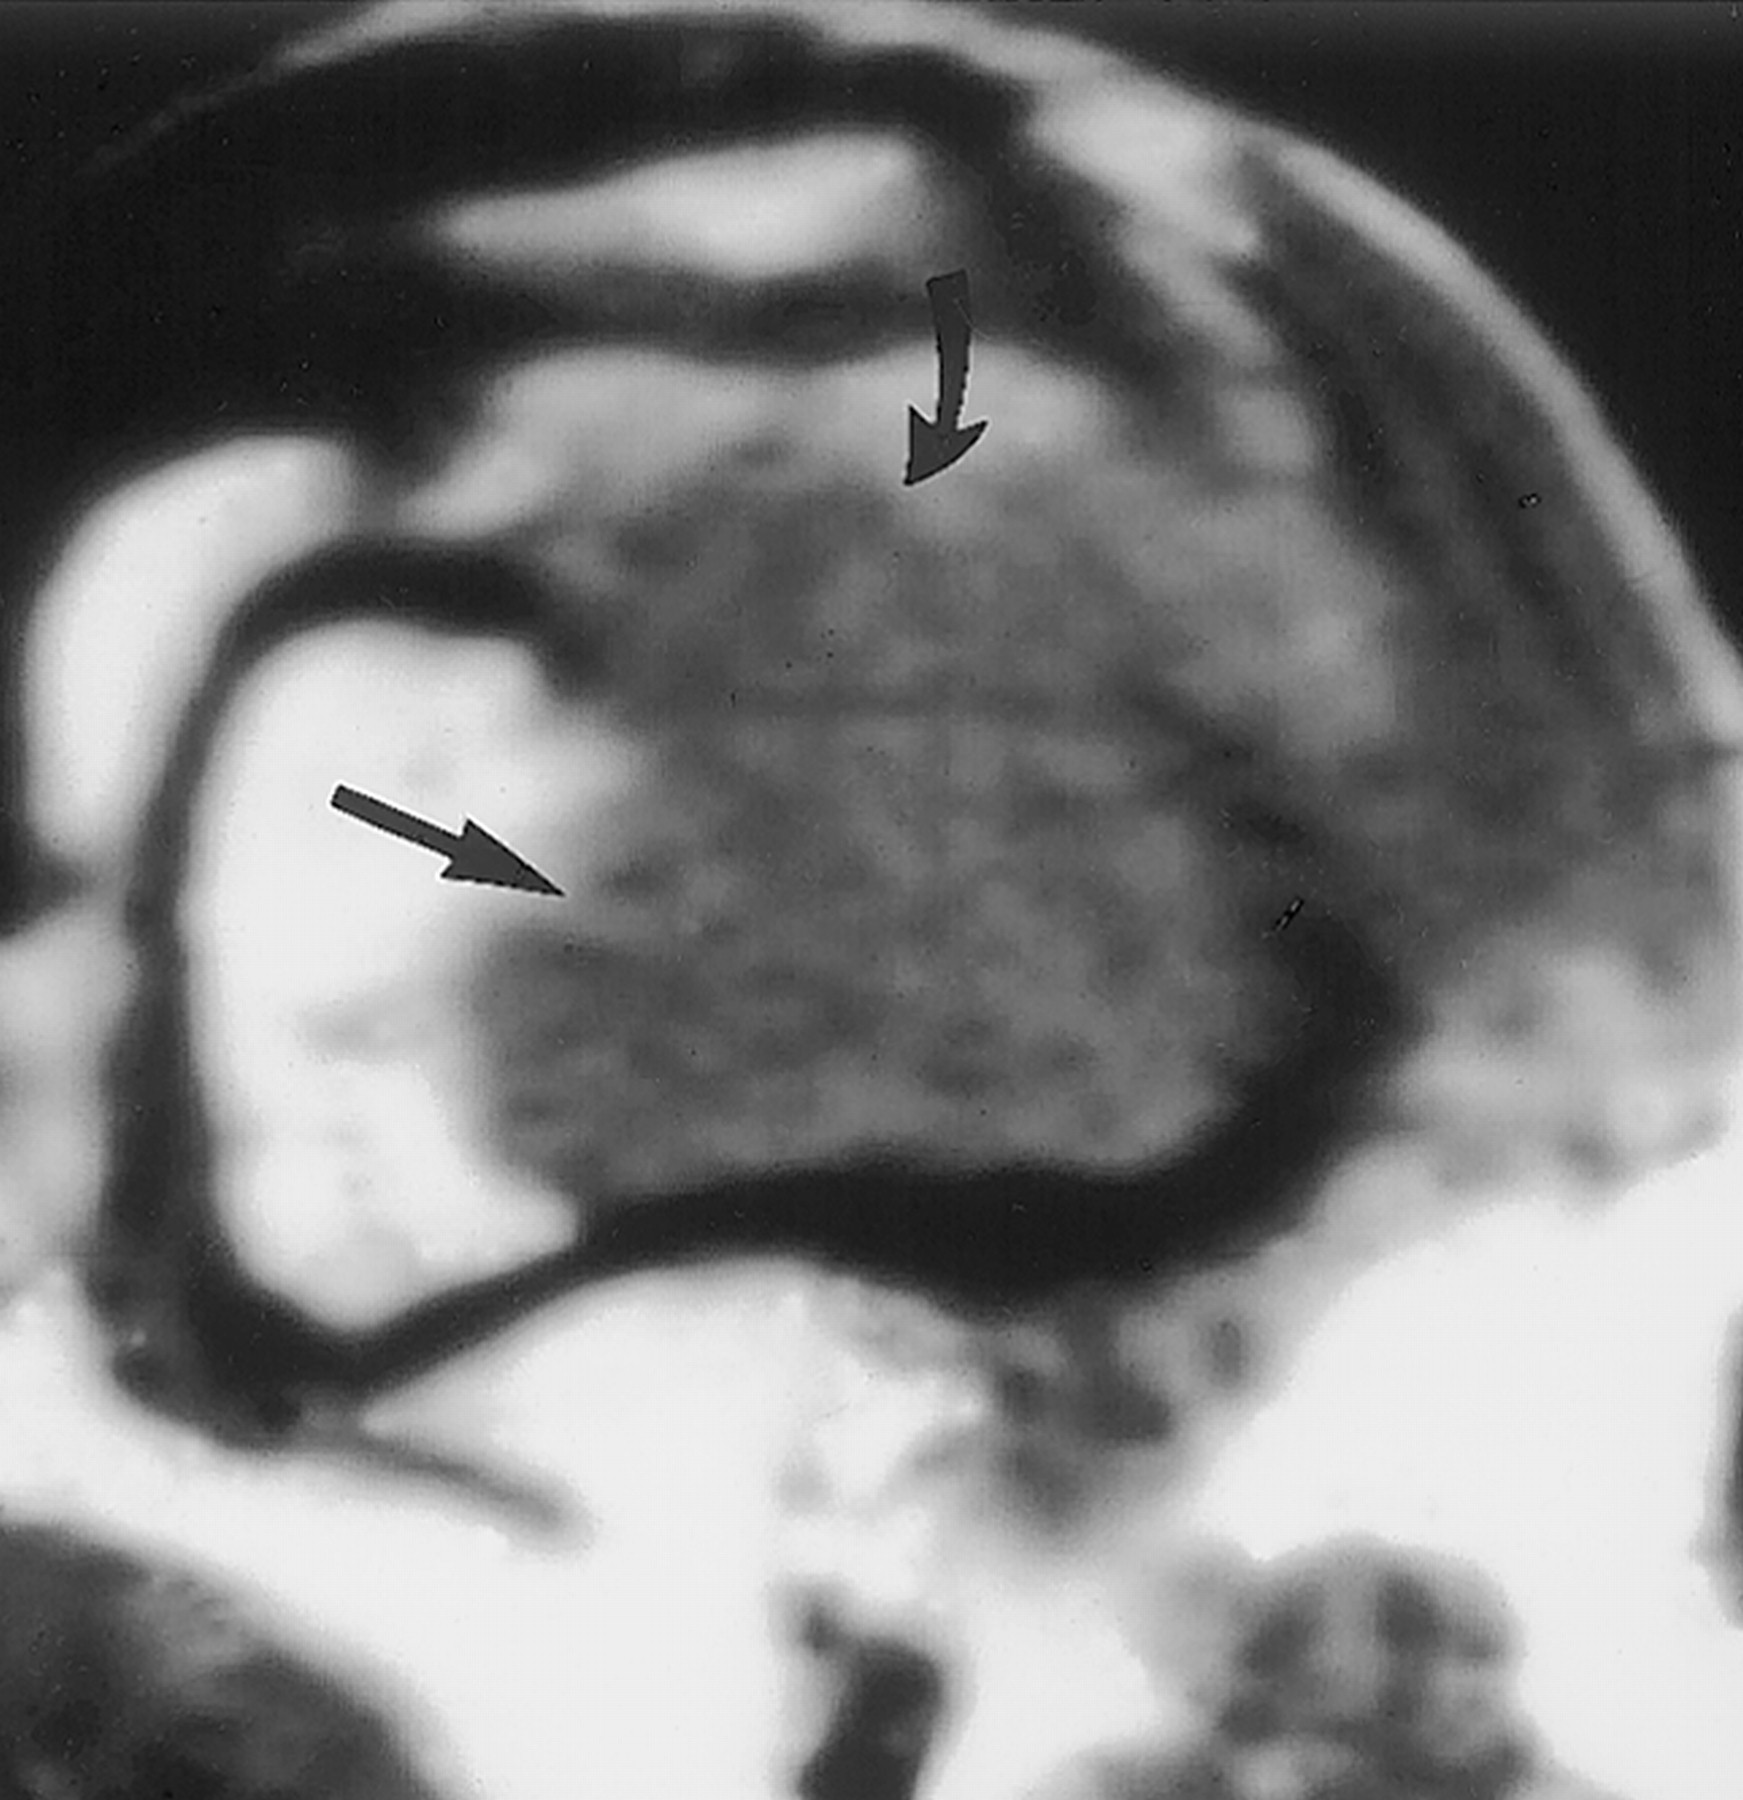

Гигантоклеточная опухоль.

Злокачественная гигантоклеточная  опухоль возникает из доброкачественной (частота 10-20%). После операции возможно появление рецидива опухоли.